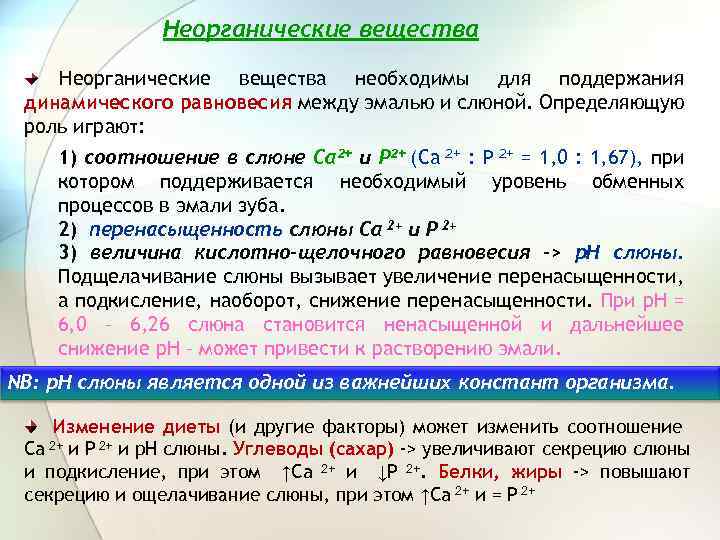

Неорганические вещества необходимы для поддержания динамического равновесия между эмалью и слюной. Определяющую роль играют: 1) соотношение в слюне Ca 2+ и P 2+ (Ca 2+ : P 2+ = 1, 0 : 1, 67), при котором поддерживается необходимый уровень обменных процессов в эмали зуба. 2) перенасыщенность слюны Ca 2+ и P 2+ 3) величина кислотно-щелочного равновесия -> p. H слюны. Подщелачивание слюны вызывает увеличение перенасыщенности, а подкисление, наоборот, снижение перенасыщенности. При p. H = 6, 0 – 6, 26 слюна становится ненасыщенной и дальнейшее снижение p. H – может привести к растворению эмали. NB: p. H слюны является одной из важнейших констант организма. Изменение диеты (и другие факторы) может изменить соотношение Ca 2+ и P 2+ и p. H слюны. Углеводы (сахар) -> увеличивают секрецию слюны и подкисление, при этом ↑Ca 2+ и ↓P 2+. Белки, жиры -> повышают секрецию и ощелачивание слюны, при этом ↑Ca 2+ и = P 2+